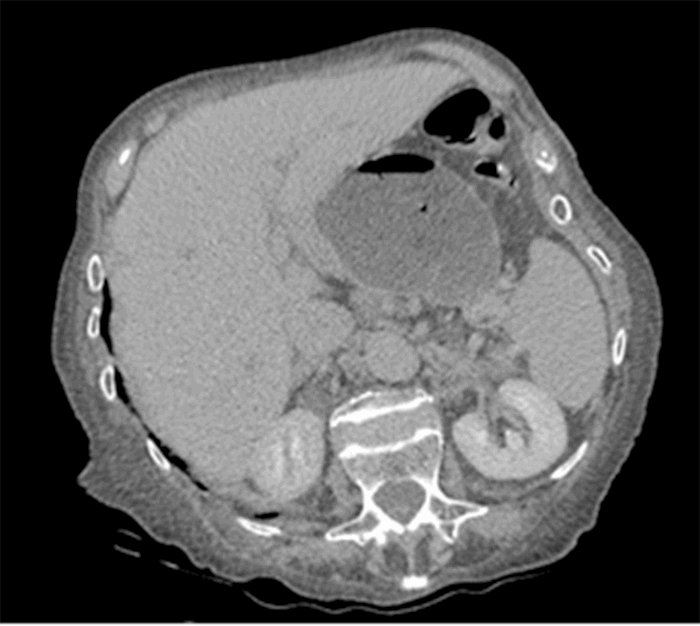

Computed tomography (CT) from outside facility performed earlier in the week revealed gastric outlet obstruction (GOO) caused by a massive type III PEH (Figure 1–4). She was subsequently discharged from this facility as she did not want surgical intervention and opted for hospice care. She presented to the ED later that week for persistent pain. At this time, it was decided to obtain a barium swallow instead of the repeat CT, demonstrating an intrathoracic stomach with concern for underlying gastric volvulus (Figure 5). Due to worsening obstructive symptoms, pain, and evidence of gastric outlet obstruction with possible gastric volvulus, it was recommended she undergo surgical intervention that day.

Figure 3. CT transverse mid-chest view.

Figure 4. CT transverse abdominal view.